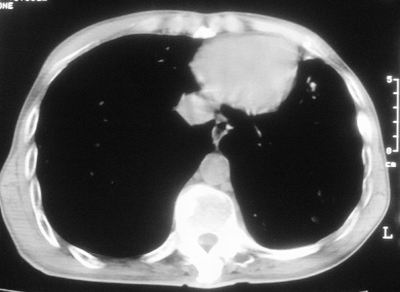

标题: CT11864:男,47岁,反复咳嗽、咯痰、咯血3年,请分析. [打印本页]

患者,男,47岁,反复咳嗽、咯痰、咯血3年,再发5天。痰培养未找到真菌、抗酸杆菌、癌细胞。

左肺上叶体积明显缩小,其内见多发透光区,纵隔向左侧移位,左肺下叶多发班片状病灶,边界模糊,1左肺上叶先天肺发育不全,2左肺下叶肺炎,

左肺上叶结核伴肺纤维化,纵隔移位,左肺下叶感染性病变,建议抗炎抗结核后复查,双肺气肿.

以下是引用xulianj在2008-2-25 21:01:00的发言:[br]左肺上叶结核伴肺纤维化有霉菌球形成,纵隔移位,左肺下叶感染性病变,建议抗炎抗结核后复查,双肺气肿.

考虑:左肺慢纤伴霉菌球形成、双肺全小叶型肺气肿。

1)考虑为:左肺上叶肺结核(空洞形成),伴左下肺感染;不排除霉菌感染可能。2)肺气肿。

左肺上叶结核伴肺纤维化空洞形成并左肺下叶感染,纵隔牵拉移位,建议作进一步检查排除左侧肺霉菌感染可能。